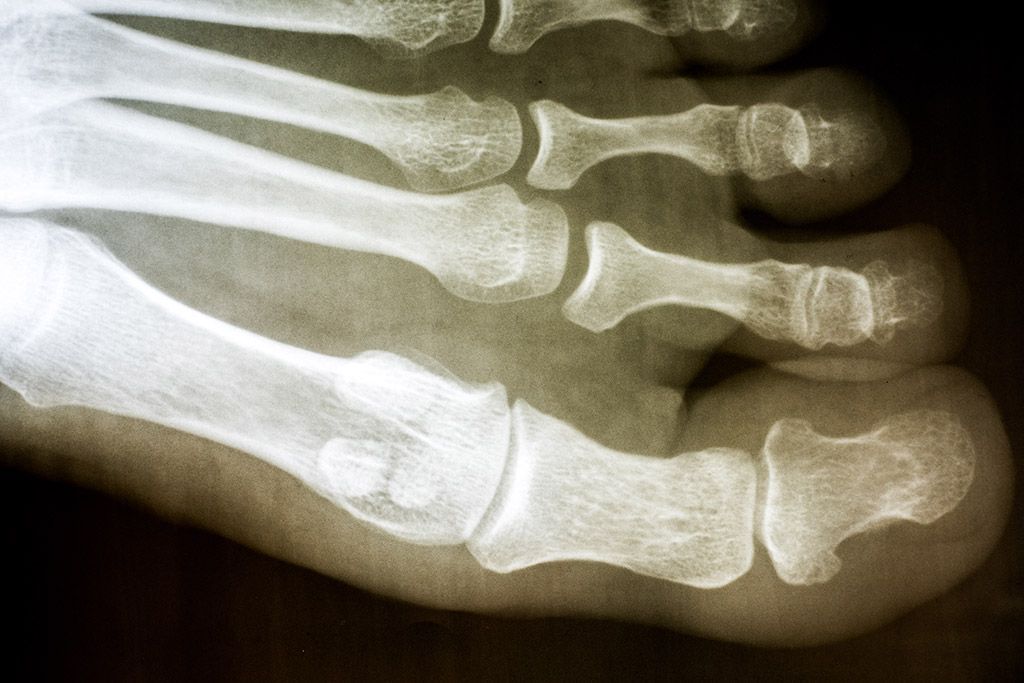

L’hallux rigidus est une arthrose de l’articulation métatarso-phalangienne de l’hallux (douleurs à la base du gros orteil). Cette dégradation arthrosique va entraîner des douleurs importantes à la marche associées à une raideur de cette articulation. On observe peu ou pas de déformation de l’axe de ce premier orteil lorsqu’il devient douloureux (contrairement à un hallux valgus). On peut observer de temps en temps une « bosse » sur le dessus de cette articulation. Il n’y a pas d’origine précise. Cette tuméfaction douloureuse est en fait un bec osseux lié à l’arthrose de l’articulation autrement appelée dorsal bunion.

Les patients sont gênés au début pour les activités intenses type course à pied ou pour le port de talons très hauts. En effet, le premier symptôme qui se développe sur l’articulation métatarso-phalangienne est la raideur. Petit à petit des douleurs s’installent, elles sont uniquement à l’effort. Rapidement, elles deviennent permanentes lors de la marche. Le dorsal bunion (bosse sur le dessus du gros orteil) apparaît à un stade relativement précoce de la pathologie. Classiquement, on décrit 4 stades dans ce type de pathologie, ces stades sont liés à la raideur de l’articulation.

Chaque stade de l’hallux rigidus peut justifier d’un traitement particulier. Le traitement de ce type de pathologie va être à la carte en fonction des malformations et des dégradations observées. Ainsi on pourra réséquer la bosse sur le dessus du gros orteil ou réduire la longueur d’un métatarsien si celui-ci semble trop long.